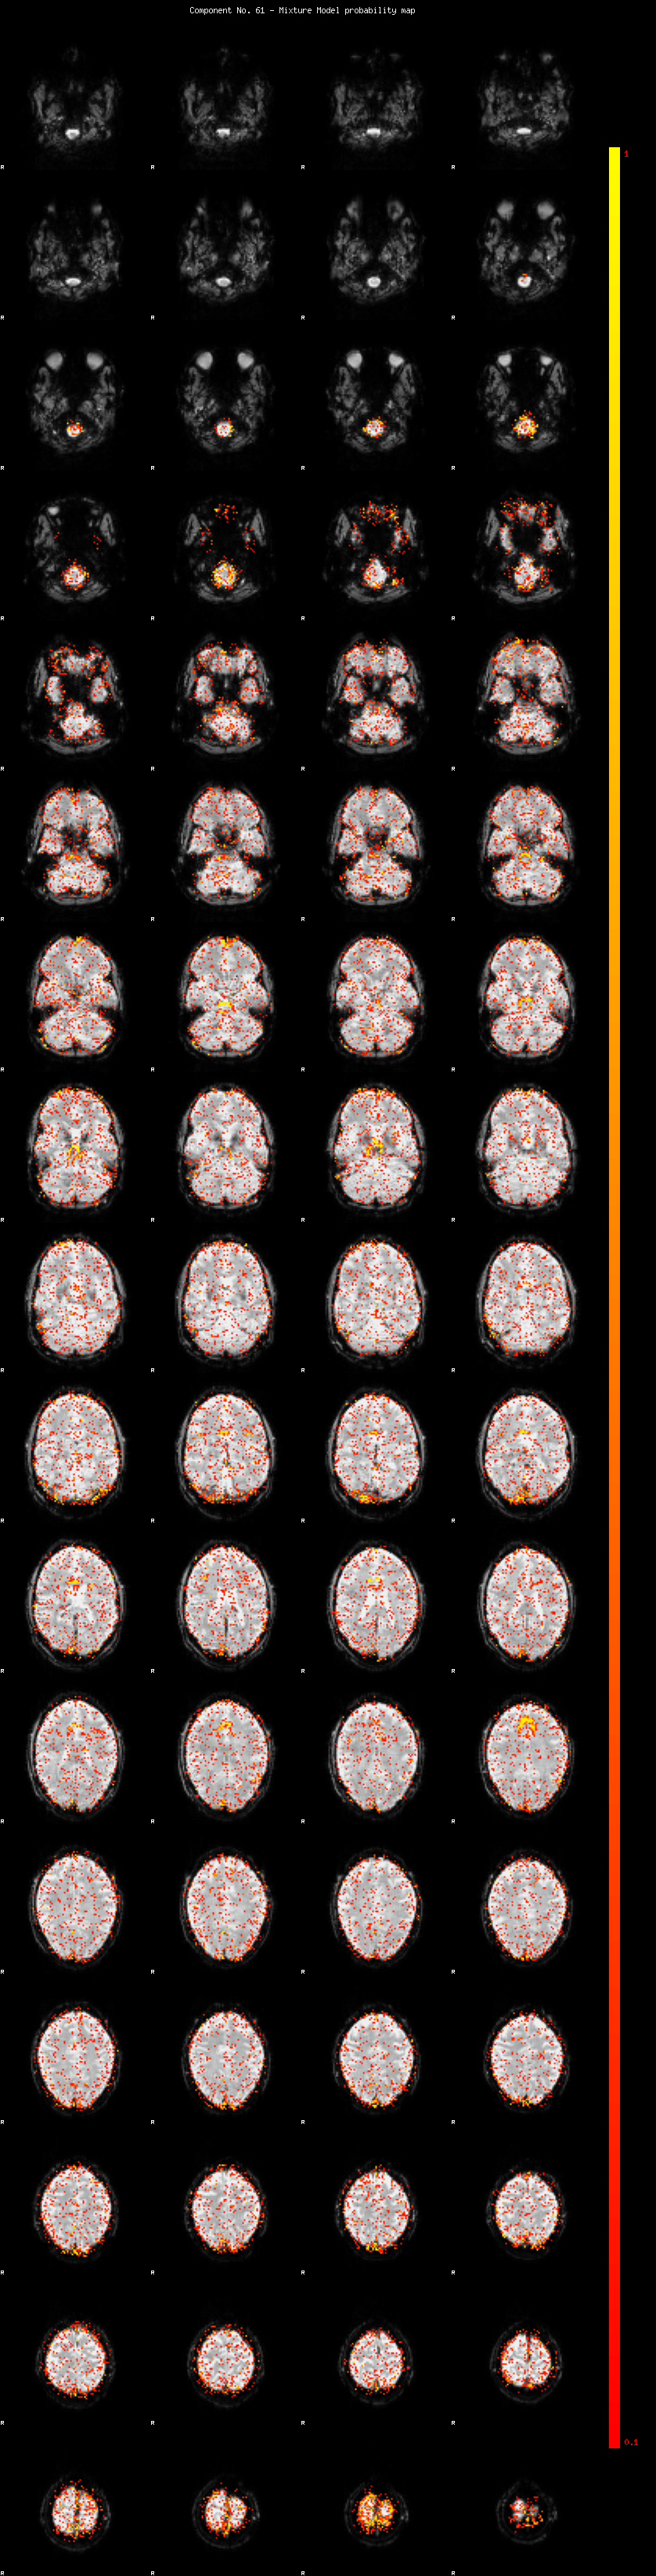

IC_61 Mixture Model fit

Means : 0.000000 2.263786 -2.155729

Vars : 1.000000 1.368815 1.073529

Prop. : 0.941875 0.028953 0.029172